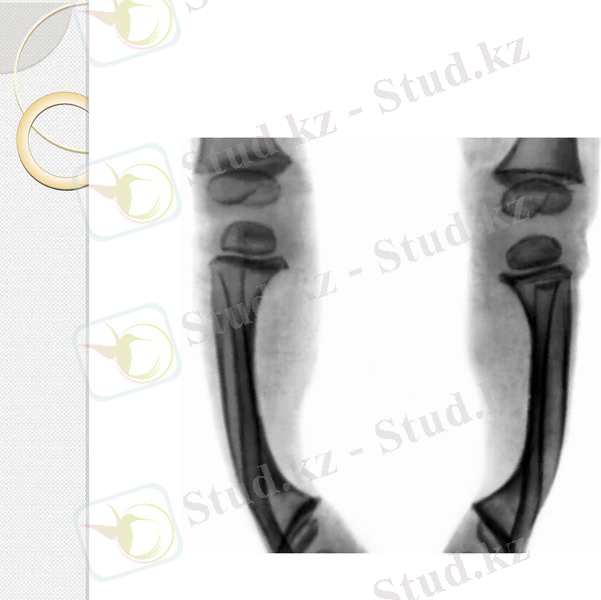

Рахит

Ол Д витамині тапшылығы мен фосфор, кальций алмасуының бұзылыстарынан дамиды. Этиологиясы:

Кальциферолдың тапшылығы кезінде аш ішекте, бүйрек өзекшелерінде кальций мен фосфордың сіңірілуі бұзылады, қанда олардың арақатынасы өзгереді. Ауру басталған кезде гипокальциемия пайда болады, ол қалқанша маңы бездері қызметінің жоғарылауына әкеледі. Соның салдарыан паратгормонның өндірілуі күшейіп, остеокластардың белсенділігі артады, сүйек тінінің ыдырауы оның түзілуінен басым болады, яғни сүйектің нәруыздық негізінің түзілуі және минералдық тұздардың жиналуы бұзылады. Нәтижесінде сүйек тінінен кальциймен фосфордың шығуы күшейіп, гиперкальциемия және гипофосфатемия пайда болады. Балаларда ағзаның өсуі тоқталады. Ересектерде сүйек тінінде тұздардың жиналуы бұзылуынан- сүйектің жұмсаруы (остеомаляция) пайда болады.

Рахиттің ең алғашқы белгісі жүйке жүйесінің өзгерістері болып табылады. Бала ашуланшақ болады, жиі жылайды, терлейді. Арнайы белгілеріне қаңқа және жілік сүйектердің өзгерістері жатады. Баланың бас сүйек еңбегі көпке дейін бітпейді, бассауыты сүйектерінің жұмсаруы байқалады. Әсіресе, кеуде қуысы сүйектері бүлінеді: қабырғалар жұмсарады, төс сүйегі алға шығып кетеді, қабырғалардың шеміршектенген жерінде мешелдік “сүйел” пайда болады. Кеуде қуысының пішіні өзгереді, алға-артқа және көлденең бағытты кеңею қабілеті жоғалады, бұл тыныстың шектелуіне өкпенің қабынуына әкеледі.